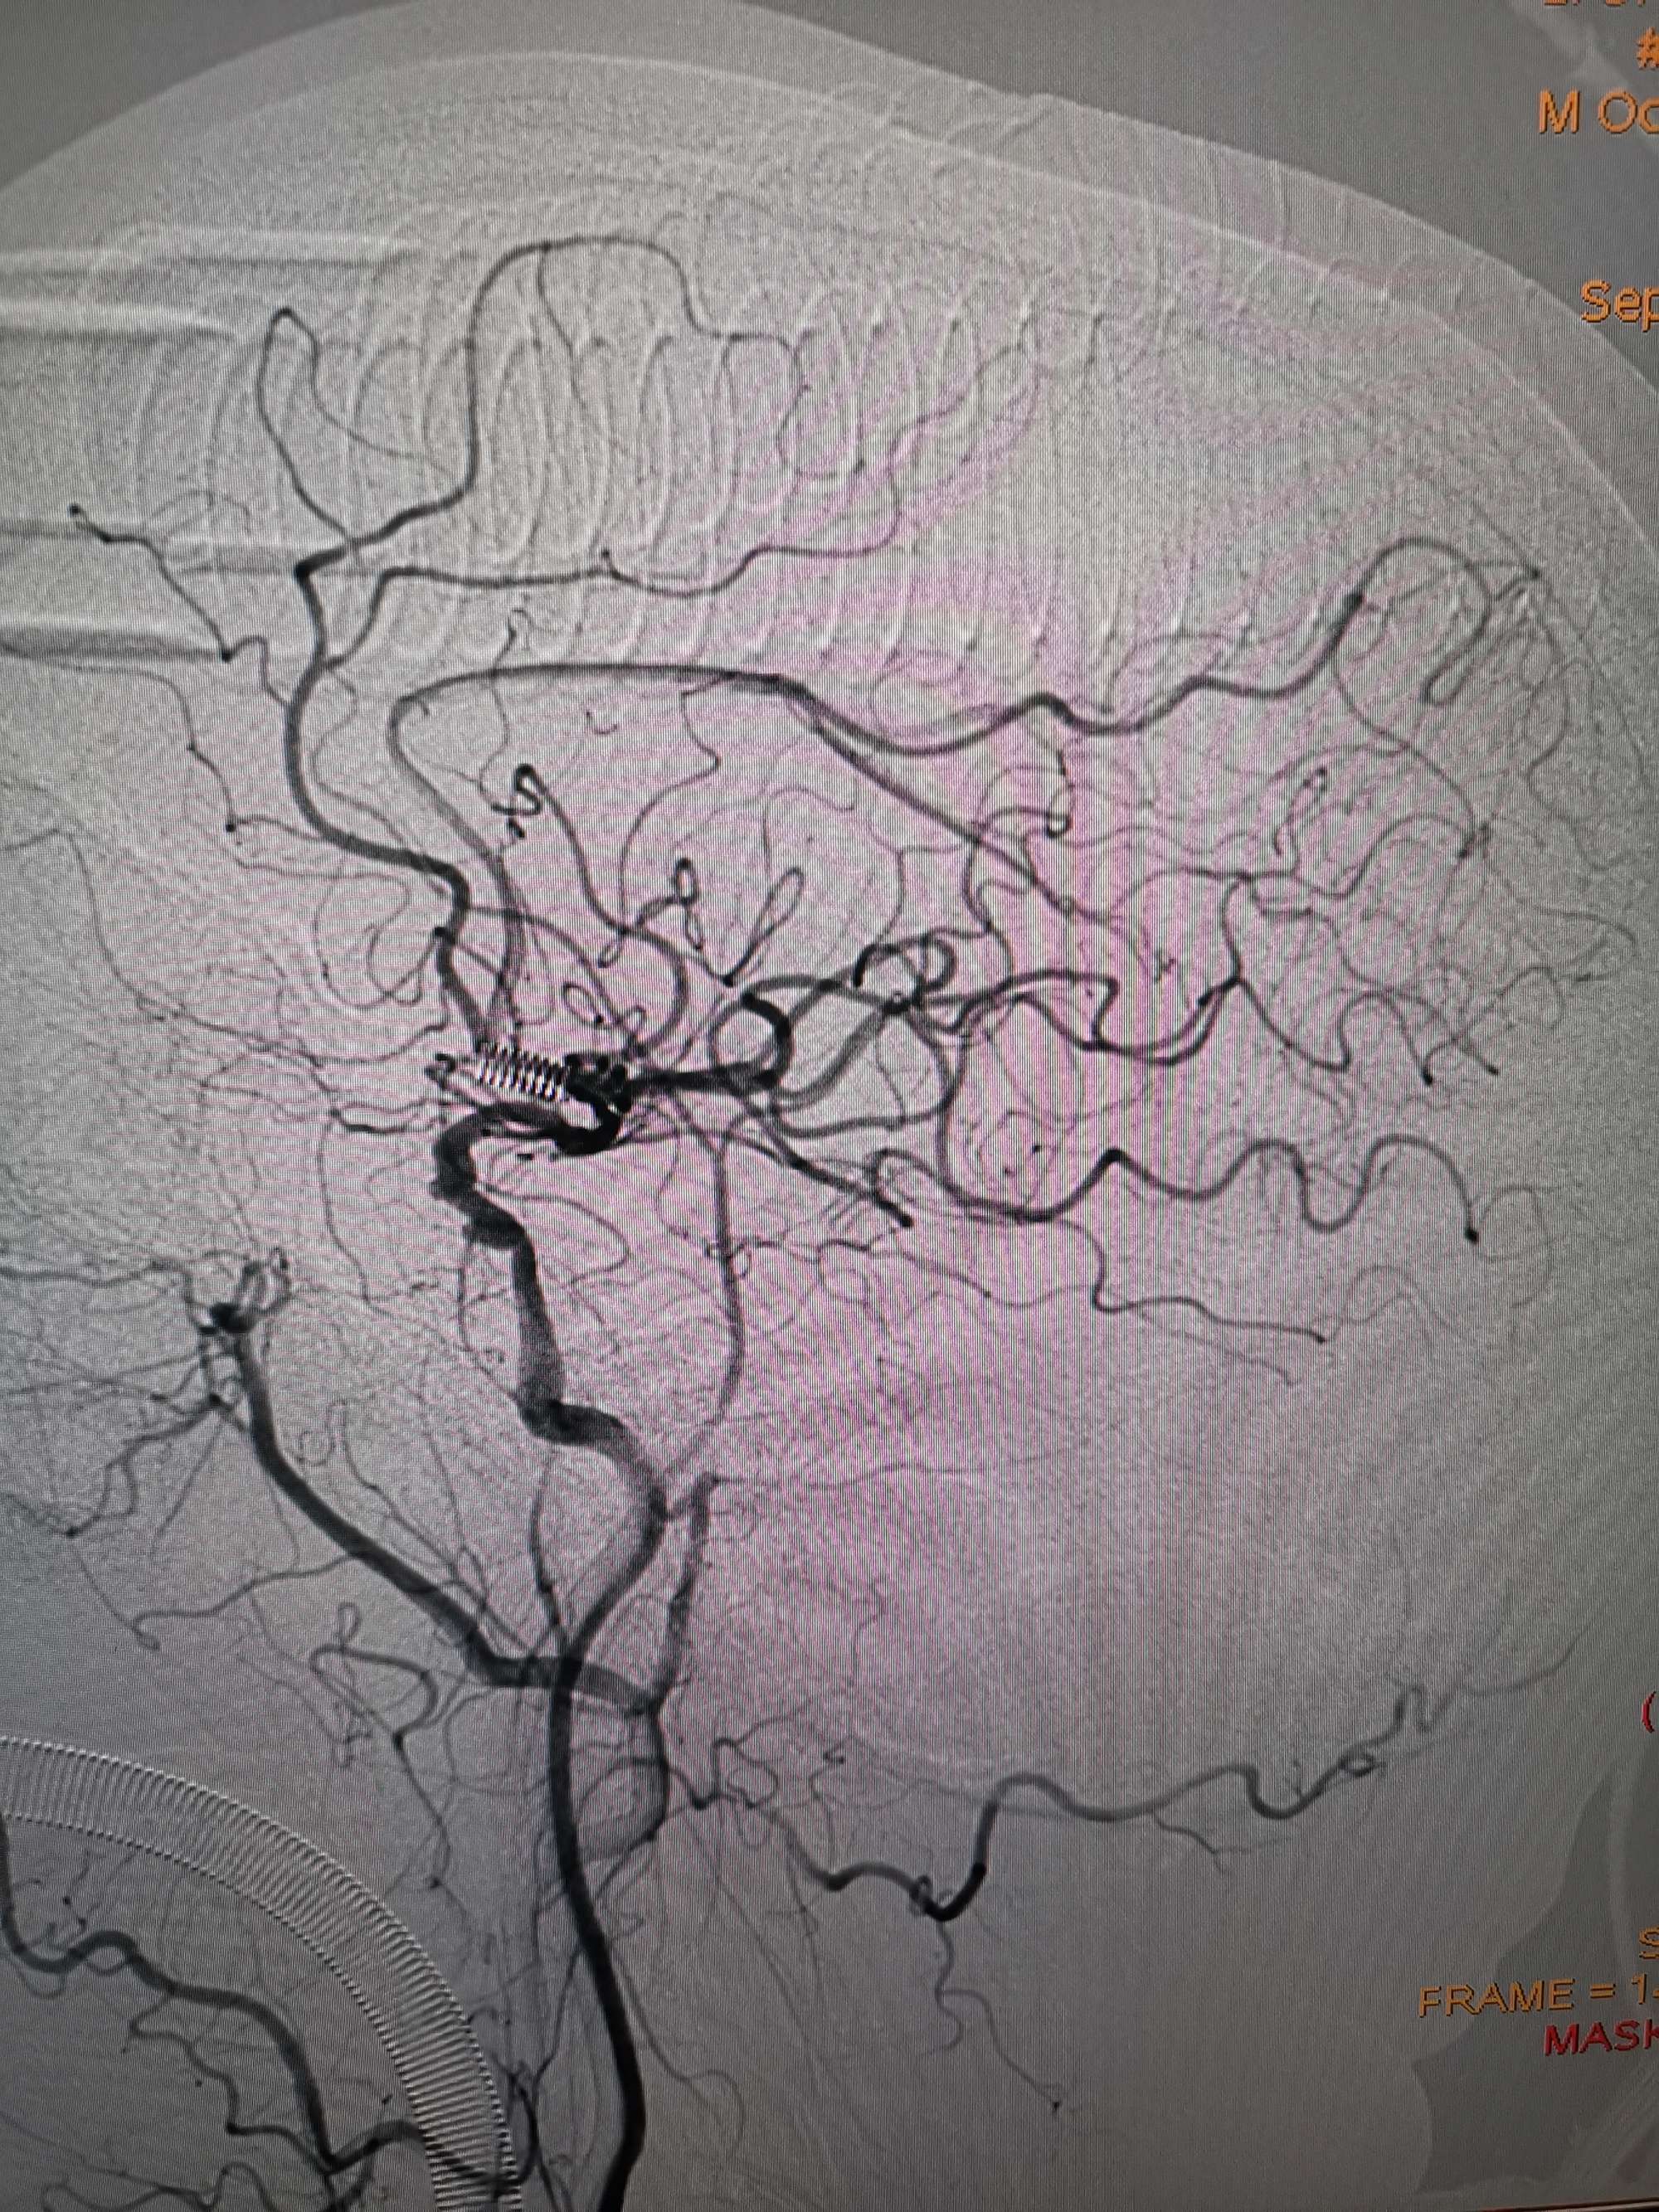

手术过程

在微导管支撑下先将微导丝和微导管穿过闭塞段,微导管超选造影证实位于基底动脉真腔后更换300cm外周交换导丝,撤出微导管后按从小到大,从远到近的原则行球囊扩张,本例手术选择了1.5✖️15、2.0✖️20、2.5✖️20球囊进行扩张,扩张满意后植入Enterprise支架,手术结束。

术后造影见左侧椎动脉闭塞段管腔恢复正常直径,远端血运良好。